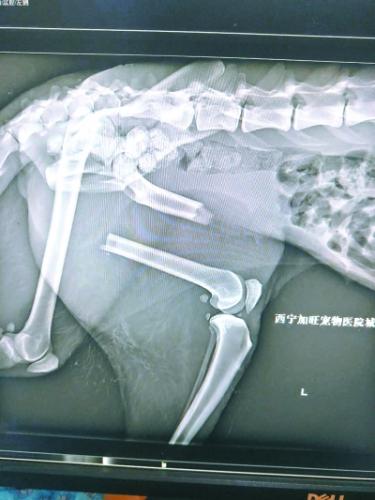

“凌雪”是一只野生老年母雪豹。去年11月末,在经历了车祸、左后腿骨折、被热心牧民发现,并转运到西宁野生动物园后,12月11日,“凌雪”接受了第一次手术,暂时保住了性命。术后,“凌雪”很快恢复活动能力,开始有跳跃行为。43天后,植入的钢钉断裂,钢板变形,第一次手术宣告失败。西宁野生动物园随即通过网络求助,经过多名兽医专家会诊,,决定运送“凌雪”来京接受第二次手术。

今年1月23日,饲养员发现“凌雪”步态异常,似乎又不能用力了。饲养员随即联系兽医,将“凌雪”麻醉后再次拉到动物医院拍片,结果令所有人大吃一惊,同时也心底一凉:“凌雪”左后肢股骨的加固钢钉折断了3根,钢板扭曲,股骨再次移位,它的腿又断了!

第一次手术植入的钢钉折断了3根

考虑到“凌雪”年事已高,已经打过11根钢钉,再次利用钢钉的话,可能会骨骼碎裂。而产生的碎骨还可能对肌肉等组织造成二次伤害,甚至感染致命。西宁野生动物园曾组织兽医和动物医院的医生进行了讨论,又向青海三甲医院的骨科专家进行了咨询,同时还向国内资深的野生动物救护人员、动物园兽医求教,但大家的意见差别很大。